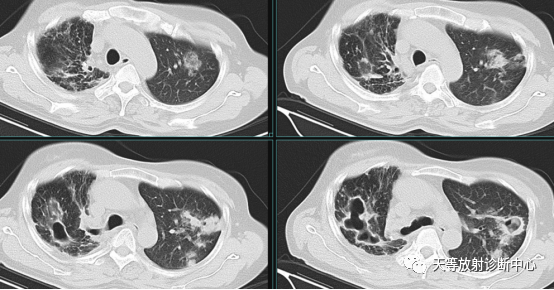

肺非结核分枝杆菌(NTM-PD)一例CT影像

女性38岁。皮肤溃疡腹腔肿瘤术后2年。肿瘤是滤泡树突状细胞肉瘤。长期免疫抑制治疗。2018-2020年肺部提示隐球菌感染。治疗效果不佳。

影像学表现:整体观察肺内多发病灶,散在分布,病灶的主要形态为:多发大小不等肺气囊、多发结节共同存在。

1、肺气囊大小不等,张力较大,圆形膨胀感强,周围可见大小不等结节影;

2、病灶主要沿支气管血管束方向分布,部分病灶达到胸膜下;

3、支气管间质增厚;

4、结节影大小不等,小的呈树芽征堆积,大的部分到达胸膜小,具有糊墙征,性格较温和。仔细观察病灶呈四边形、多边形,边缘刀切感,边界模糊。

病理结果:NTM-鸟分支杆菌